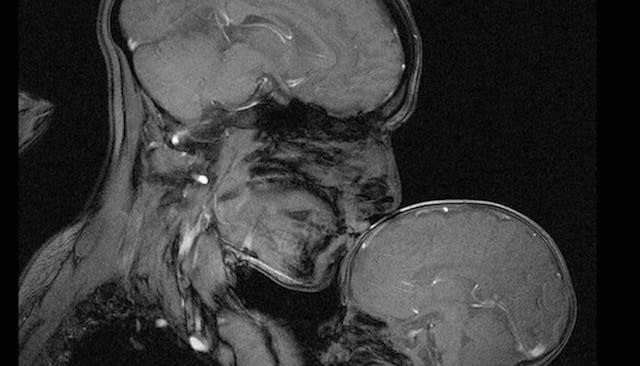

An MRI is often used to find tumors or blocked blood vessels, but a neuroscientist recently used the technology to capture something much sweeter. Rebecca Saxe, a professor of cognitive neuroscience at MIT, recently released this breathtaking image of her cuddling and kissing her two-month-old son, Percy, inside an MRI machine.

The image is striking for a lot of reasons. First, as Saxe points out to Today, there are the mom and infant brains. She says some people look at it and see “how thin his skull is; how little space there is between the world outside and his brain.” Others notice how similar an infant’s brain is to their mother’s and “how close in size – so much closer in size than his hand.”

The other thing that’s so stunning is the relationship the image depicts. You can’t see any surface details and yet, the bond is plainly evident. You can see how fragile the infant is, and the strong and protective universal figure of a mom. As Saxe writes in her Smithsonian piece, “… the two figures, with their clothes and hair and faces invisible, become universal, and could be any human mother and child, at any time or place in history.”